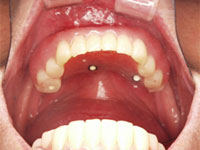

(1)下顎にオールオン4インプラント治療を行う

手術したその日からまともに食事ができるように手術したその日に仮の歯を入れる。

手術したその日からまともに食事ができるように手術したその日に仮の歯を入れました。.